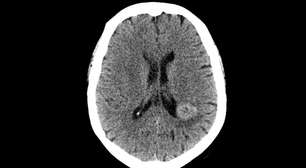

A sensibilidade a luz é um sintoma frequente entre crises de dor de cabeça -

Foto: Shutterstock / Alto Astral